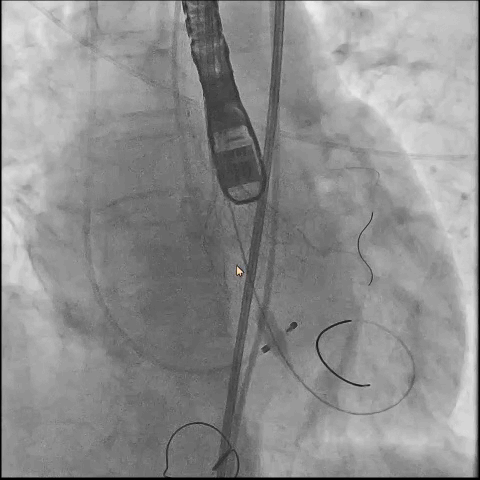

● 更换新瓣膜跨瓣后,猪尾难以送至无冠窦底,故行造影定位窦底。

隐约可见“无冠窦”后部更深窦底,位于“无冠窦”下约6mm,参考该位置后进行0位定位,无起搏逐步释放至工作位,瓣膜无明显位移表现,瓣膜形态压缩良好,造影评估无反流。准备释放瓣膜。

无张力释放,脱钩后瓣膜略微下滑,约位移瓣环下4~5mm位置,瓣膜整体形态良好,造影评估无可见反流。

超声评估,微量瓣周反流,二尖瓣工作良好,植入位置理想。

结束手术,一波三折终成功!